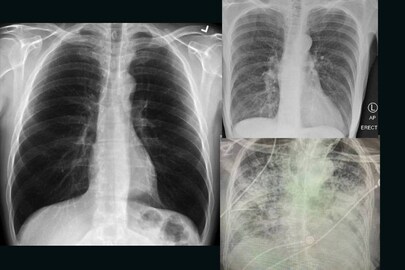

ശ്വാസകോശം സ്പോഞ്ച് പോലെയാണെന്ന് ഏത് കൊച്ചുകുട്ടിക്കും അറിയാം. കാരണം നമ്മൾ ദിനംപ്രതി കേൾക്കുന്ന പുകവലി വിരുദ്ധ പരസ്യങ്ങൾ തന്നെ കാരണം. എന്നാൽ, ഈ സ്പോഞ്ച് പോലെയുള്ള ശ്വാസകോശത്തിനോട് പുകവലി ചെയ്യുന്നതിനേക്കാൾ വലിയ ദ്രോഹമാണ് കോവിഡ് ചെയ്യുന്നതെന്നാണ് റിപ്പോർട്ടുകൾ. കോവിഡ് ബാധിച്ച് സുഖം പ്രാപിച്ച് എത്തുന്ന ഒരാളുടെ ശ്വാസകോശം പുകവലിക്കാരുടെ ശ്വാസകോശത്തേക്കാൾ മോശമായി അവസ്ഥയിൽ ആയിരിക്കുമെന്നാണ് റിപ്പോർട്ട്.

കോവിഡിൽ നിന്ന് മുക്തി നേടിയ രോഗികളുടെ ശ്വാസകോശത്തിൽ കാണപ്പെടുന്ന പരിക്കുകളും പാടുകളും പുകവലിക്കാരുടെ ശ്വാസകോശത്തിൽ കാണുന്നതിനേക്കാൾ മോശമാണെന്നാണ് റിപ്പോർട്ട്. ടെക്സാസ് ടെക് യൂണിവേഴ്സിറ്റി ഹെൽത്ത് സയൻസ് സെന്ററിലെ അസിസ്റ്റന്റ് പ്രൊഫസർ ആയ ഡോ ബ്രിട്ടാനി ബാങ്ക് ഹെഡ് കെന്റൽ ആണ് എക്സ് റേ ചിത്രങ്ങൾ പുറത്തുവിട്ടത്. കഴിഞ്ഞവർഷം മഹാമാരി പടർന്നു പിടിച്ചതു മുതൽ ആയിരക്കണക്കിന് രോഗികളെ കോവിഡ് രോഗികളെ ചികിത്സിച്ച ഡോക്ടറാണ് അദ്ദേഹം.

സാധാരണ ആരോഗ്യമുള്ള ഒരാളുടെ ശ്വാസകോശവും ഒരു പുകവലിക്കുന്ന ആളുടെ ശ്വാസകോശവും കോവിഡ് ബാധിച്ച ഒരാളുടെ ശ്വാസകോശവുമാണ് ഇവർ പങ്കുവച്ചത്. സാധാരണ ശ്വാസകോശം ഇരുണ്ടതും കാണാവുന്നതുമാണ്.

പുകവലിക്കുന്ന ആളുടെ ശ്വാസകോശം

പുകവലിക്കുന്ന ആളുടെ ശ്വാസകോശം ഭാഗികമായി വെളുത്തതാണ്. എന്നാൽ, കൊറോണ വൈറസ് രോഗിയുടെ ശ്വാസകോശം കാണാൻ കഴിയാത്ത വിധത്തിലുള്ളതാണ്.

കോവിഡ് ബാധിച്ചതിനു ശേഷമുള്ള ശ്വാസകോശം

ട്വിറ്ററിലാണ് അദ്ദേഹം ഇക്കാര്യം പങ്കുവച്ചത്. കോവിഡ് ബാധിച്ചതിനു ശേഷമുള്ള ശ്വാസകോശം നല്ലൊരു പുകവലിക്കാരന്റെ ശ്വാസകോശത്തേക്കാൾ മോശമാണെന്നും അദ്ദേഹം കുറിക്കുന്നു. ശ്വാസതടസം ഉൾപ്പെടെയുള്ള അസ്വസ്ഥതകൾക്ക് അത് കാരണമാകുന്നു.